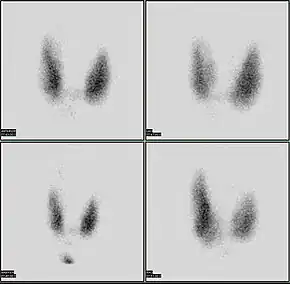

A thyroid scan using a radioactive iodine uptake test can be used in viewing the thyroid.[19] A scan using iodine-123 showing a hot nodule, accompanied by a lower than normal TSH, is strong evidence that the nodule is not cancerous, as most hot nodules are benign.

Thyroid scan

85% of nodules are cold nodules, and 5–8% of cold and warm nodules are malignant.[27]

5% of nodules are hot. Malignancy is virtually non-existent in hot nodules.[28]